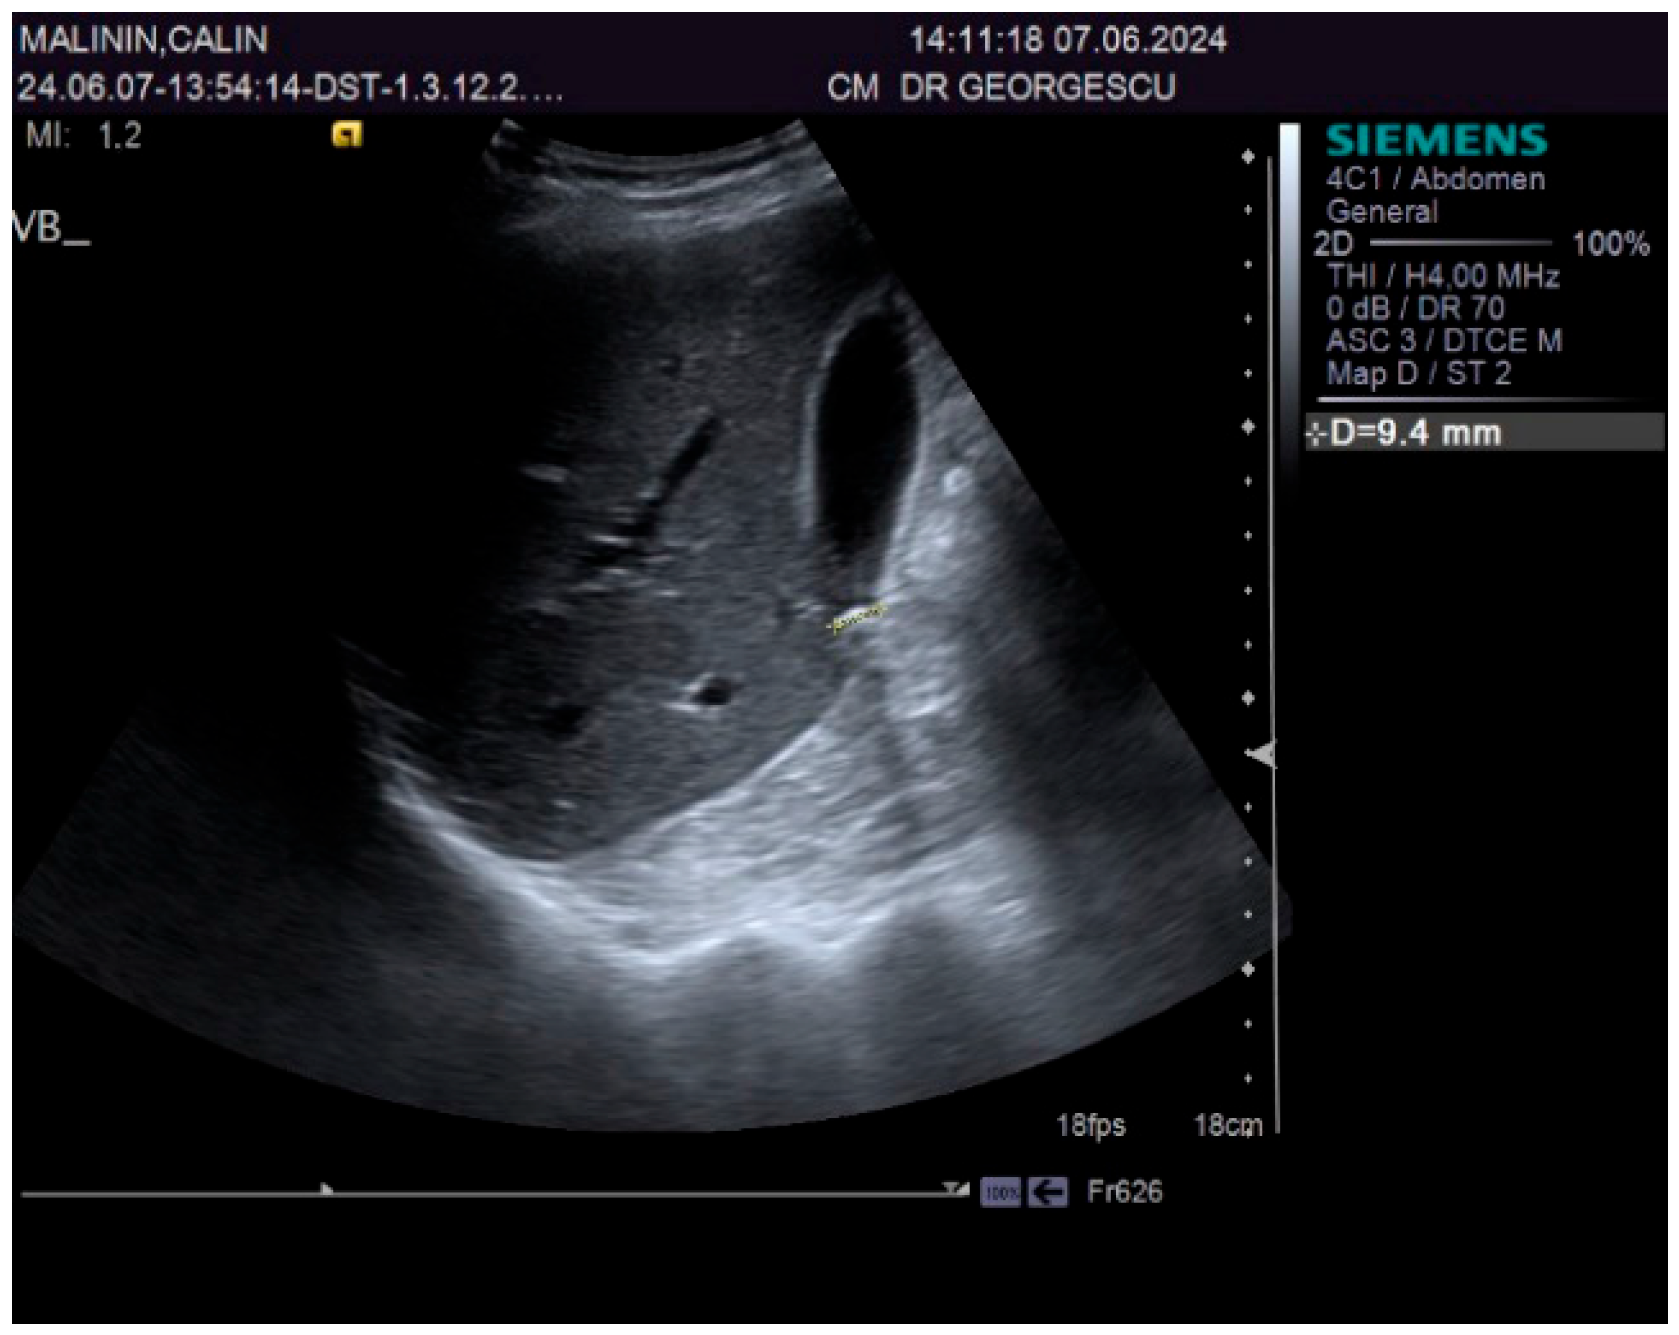

2. Case Report